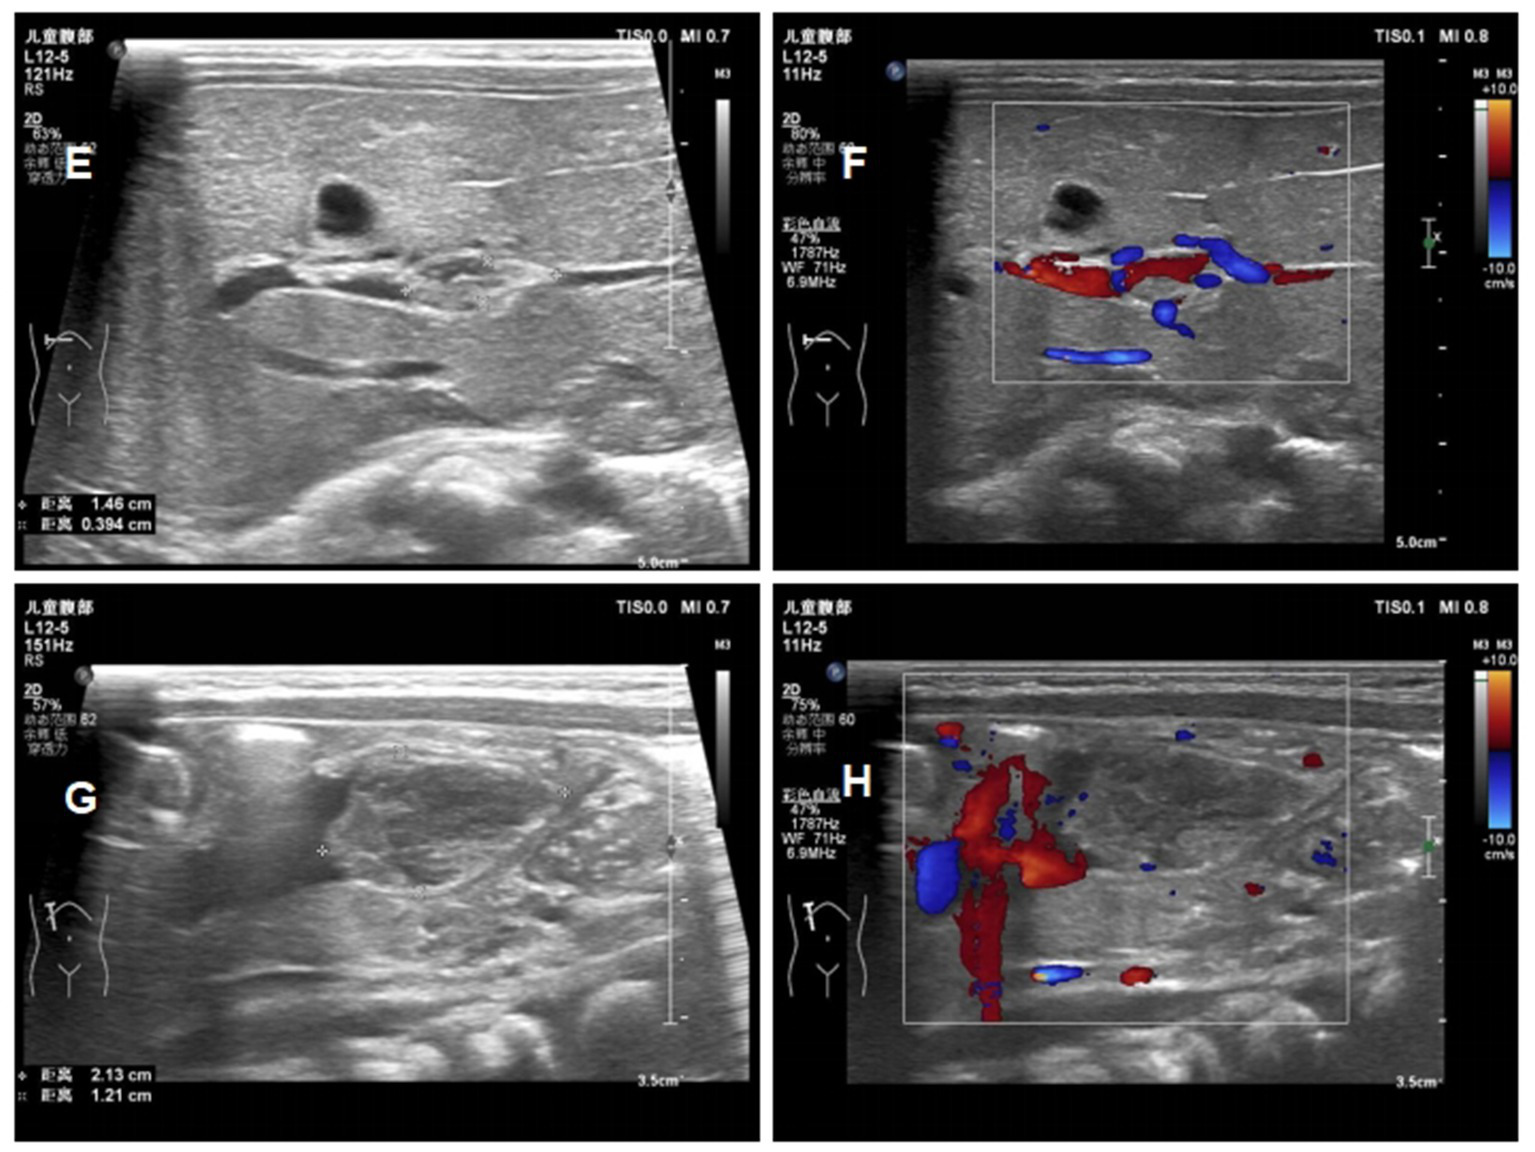

At day 16 of life, a fourth ultrasound showed that the thrombus was significantly smaller than before, and the stenosis degree of the portal vein decreased from 75 to 30% (Figure 5). Laboratory tests showed that Protein C had risen to 40%. Therefore, the baby was discharged in good clinical condition and with enoxaparin (2.1 mg/kg q12h) to be continued Table 2 shows the fetal hematology test indicators and Table 3 for pregnant woman.

Figure 5

Ultrasound images of the patients ont day 16 of life (E) reduction in the size of the portal vein thrombus at day 16; (F) the blood flow signal of portal vein thrombosis at day 16; (G) reduction in the size of the umbilical vein thrombus at day 16; (H) the blood flow signal of umbilical vein thrombosis at day 16.